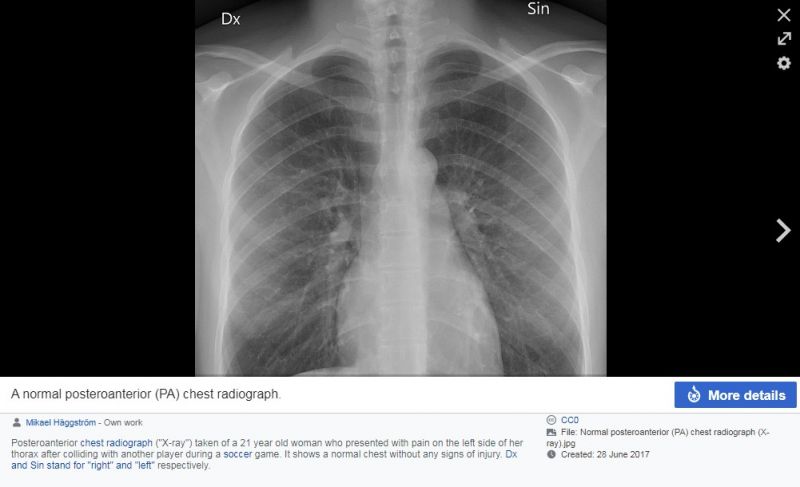

ਸਾਨੂੰ ਅਸਲ ਤਸਵੀਰ “radlines.org” ਨਾਂਅ ਦੀ ਵੈੱਬਸਾਈਟ ‘ਤੇ ਅਪਲੋਡ ਮਿਲੀ। ਅਸਲ ਤਸਵੀਰ ਵਿਚ X-Ray ਰਿਪੋਰਟ ਅੰਦਰ ਕੀਤੇ ਵੀ ਕੋਕਰੋਚ ਨਹੀਂ ਦਿੱਸ ਰਿਹਾ ਸੀ। ਇਸ ਤਸਵੀਰ ਨਾਲ ਕੈਪਸ਼ਨ ਲਿਖਿਆ ਗਿਆ ਸੀ: “A normal posteroanterior (PA) chest radiograph”

ਇਥੇ ਮੌਜੂਦ ਜਾਣਕਾਰੀ ਅਨੁਸਾਰ, "ਇਹ X-Ray 21 ਸਾਲ ਦੀ ਔਰਤ ਦਾ ਲਿਆ ਗਿਆ ਹੈ ਜਿਸ ਦੀ ਇੱਕ ਸੋਕਰ ਗੇਮ ਦੌਰਾਨ ਕਿਸੇ ਖਿਡਾਰੀ ਨਾਲ ਟੱਕਰ ਹੋਈ ਅਤੇ ਬਾਅਦ ਵਿਚ ਉਸ ਦੇ ਛਾਤੀ ਦੇ ਖੱਬੇ ਪਾਸੇ ਵਿਚ ਦਰਦ ਉੱਠ ਖੜ੍ਹਿਆ ਸੀ।"